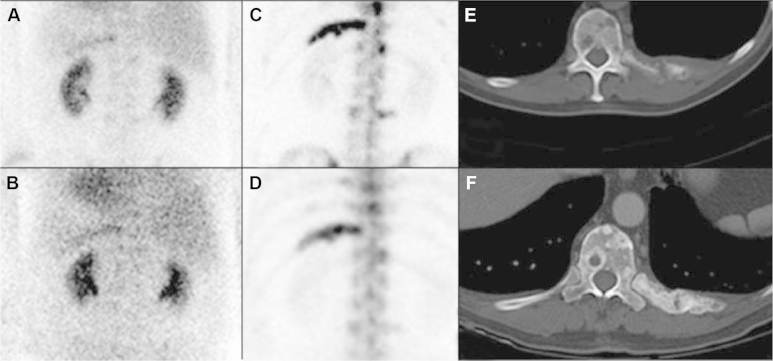

Figure 3.

Pre-chemotherapy blood pool (A) and delay (C) shows increased uptake in the left 11th rib corresponding to lytic metastasis on axial CT (E). One month post-chemotherapy blood pool (B) and delay (D) shows persistent, but decreased uptake on left 11th rib with positive post-treatment sclerosis on axial CT (F).

One month follow up CT scan demonstrated sclerotic lesions with minimal evidence of active metastatic disease; however bone scan still showed multiple uptake areas consistent with active disease. Current literature for hormone sensitive prostate cancer with lytic bone lesions stems from breast cancer management; CT scan in this patient provides evidence of successful treatment suggested by sclerotic lesions as is seen in breast and prostate cancer patients post-chemotherapy.1, 2, 3 However, there is no data with timing recommendations for bone scan to evaluate successful treatment outcome of prostate cancer with metastatic lytic lesions (Fig. 3).